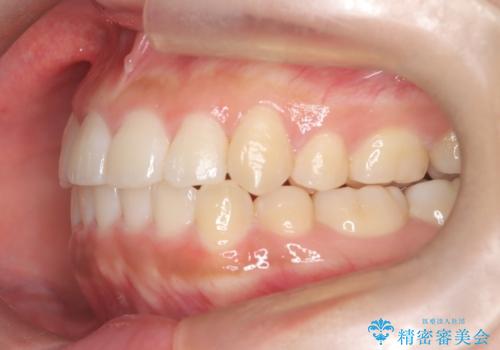

- 前歯のでこぼこが気になると来院されました。

奥歯の噛み合わせは綺麗に噛んでいたため、前歯の叢生(でこぼこ)を、短期間で治療完了するように計画しました。

前歯のガタツキを改善する治療法として、マウスピース矯正が適していることが多いです。

マウスピース矯正は、金属製のブラケットやワイヤーを使用せずに、透明なマウスピースを装着して歯を移動させる方法です。そのため、目立たず、痛みも少ないです。